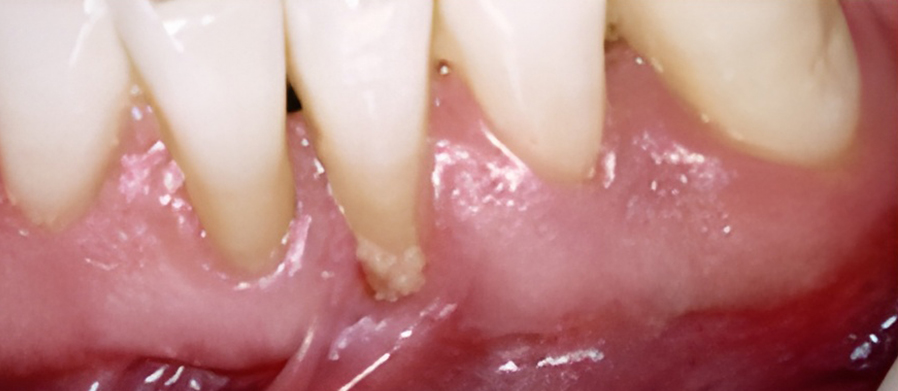

치은염을 치료하지 않고 방치하면 플라그가 뿌리로 퍼져 뼈와 연조직에 감염과 손상을 일으킬 수 있습니다. 잇몸이 치아에서 분리되어 물러나기 시작할 수 있으며 잇몸 라인 아래에 주머니가 생겨 플라크와 음식물이 쌓일 수 있습니다.

잇몸이 심하게 붓고 피가 자주 나며 치가가 흔들리기도 합니다. 치아 뿌리가 드러나기도 하며 때로는 잇몸에 고름이 나와 음식물을 잘 씹을 수가 없습니다.